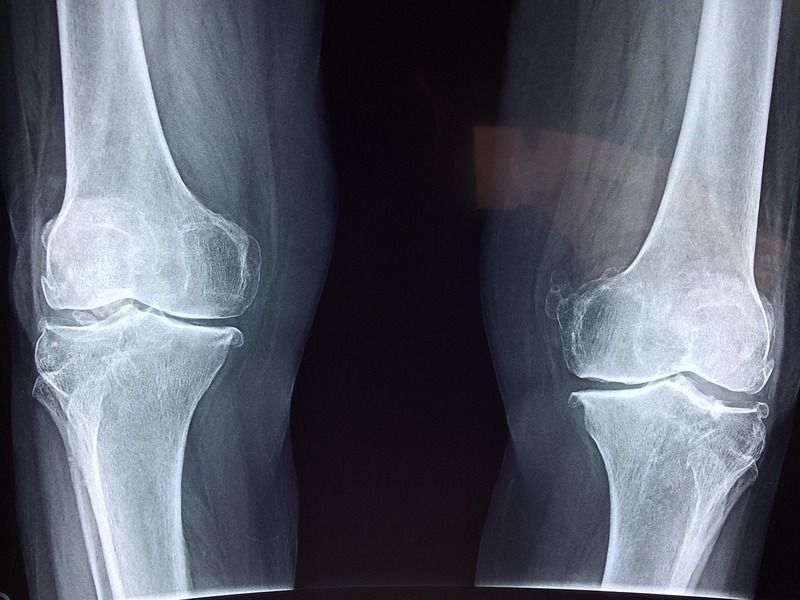

La pose d’une prothèse du genou est envisagée lorsque les traitements non chirurgicaux ne permettent plus de contrôler les symptômes. Les douleurs deviennent alors constantes, y compris au repos, et s’accompagnent d’une raideur marquée limitant les déplacements. L’usure avancée du cartilage, confirmée par l’imagerie, entraîne une altération mécanique irréversible de l’articulation. La gêne fonctionnelle impacte directement la vie quotidienne, la marche, la montée des escaliers ou les activités professionnelles. La décision repose aussi sur l’échec des infiltrations, de la rééducation et des traitements médicamenteux.

La prothèse du genou remplace les surfaces articulaires altérées par des composants artificiels conçus pour reproduire le mouvement naturel. L’implantation respecte l’axe du membre inférieur et l’équilibre ligamentaire. Après l’opération, l’organisme doit intégrer cette nouvelle articulation. Une phase d’apprentissage s’installe, durant laquelle le cerveau ajuste les schémas moteurs. Les matériaux utilisés permettent une glisse adaptée et une résistance à l’usure. Le but consiste à restaurer une articulation stable, indolore et fonctionnelle, capable de supporter les contraintes du quotidien sans générer de frottements pathologiques.